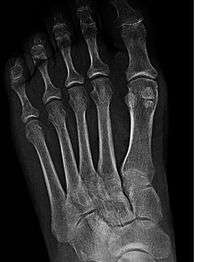

![]() Bones of the right foot. Dorsal surface. The first metatarsal bone is shown in yellow farthest to the left | |